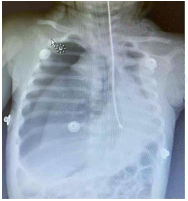

Durante a intercorrência, um interno aparece

com uma radiografia de tórax do paciente que

havia sido realizada à admissão.